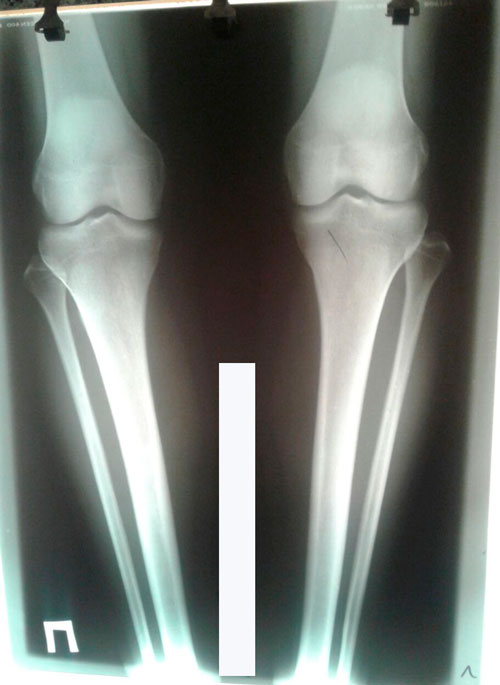

Дата операции 28.04.2017г.

Дата снятия аппаратов 05.10.2017г.

Срок лечения 150 дней.

PS. из за личных обстоятельств, снятие аппаратов затянулось. Но пациентку это не беспокоило.